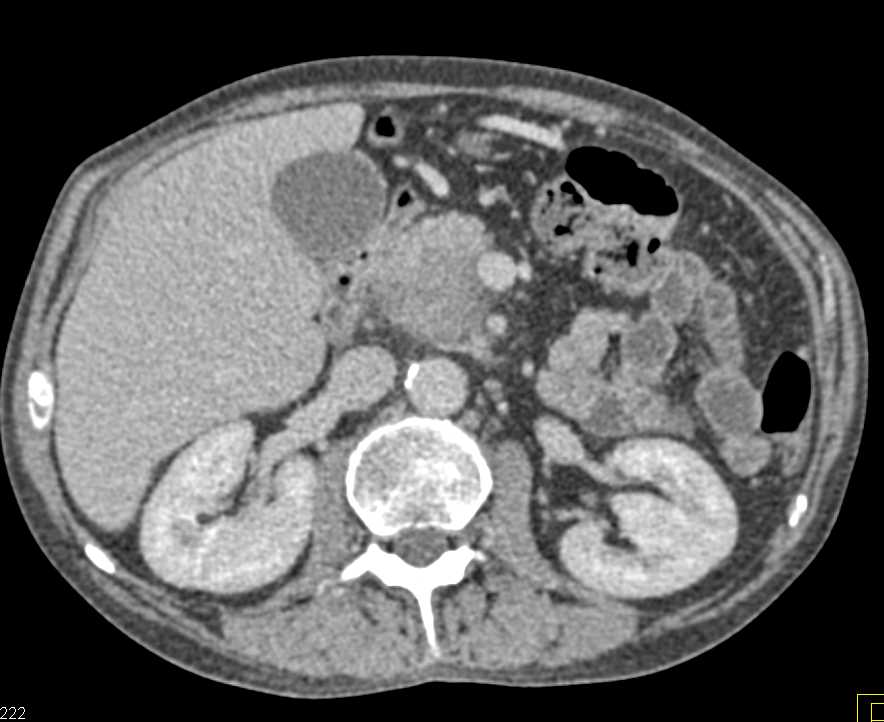

Acute Cholecystitis